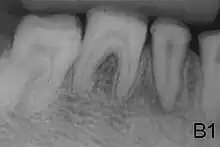

- Enamel has sound thickness, with a pitted appearance. It is less hard compared to normal enamel, and are prone to rapid wear, although not as intense as Type 3 AI. Condition is of autosomal dominant, autosomal recessive, or x-linked pattern. Enamel appears to be comparable to dentine in its radiodensity on radiographs.